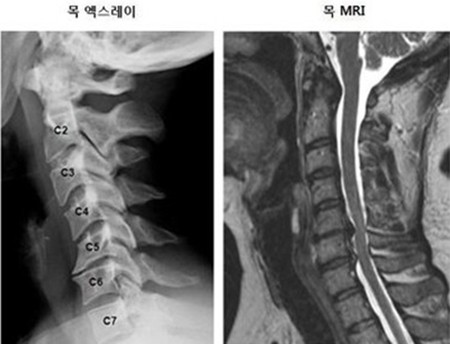

목 디스크는 목의 디스크(경추 디스크)에서 출현하는 질환으로, 경추 디스크 사이의 연골판이 터져 디스크 내부 물질이 경추 신경을 자극해 통증이나 저림증 등의 증상을 유발 해요. 목 디스크는 일상생활에서의 안 좋은 자세나 많은 운동, 부상 등이 이유가 되는 것이 될 수 있기도하고, 시간이 지날수록 발생 확률이 높아져요. 목 디스크의 증상으로는 목 부위의 통증, 팔의 저림, 근육 약화 등이 있으며, 증상이 난폭한 경우 수술 등의 치료가 필요할 수 있어요. 그리하나 대개의 경우 치료 없이도 시간이 지나면 증상이 호전되는 경우가 대부분입니다.

목디스크 증상 목 자세이고요. 현대인들은 스마트폰이나 모니터를 많이 사용하다보니 목이 앞쪽으로 당겨져있는 것처럼 자세를 많이 취하게 된다 하였습니다. 이런 자세는 정상적인 목뼈를 전환 시켜 여러분이 아시는 거묵목 증상이 나타나게 되는 이유가 되는 것입니다.